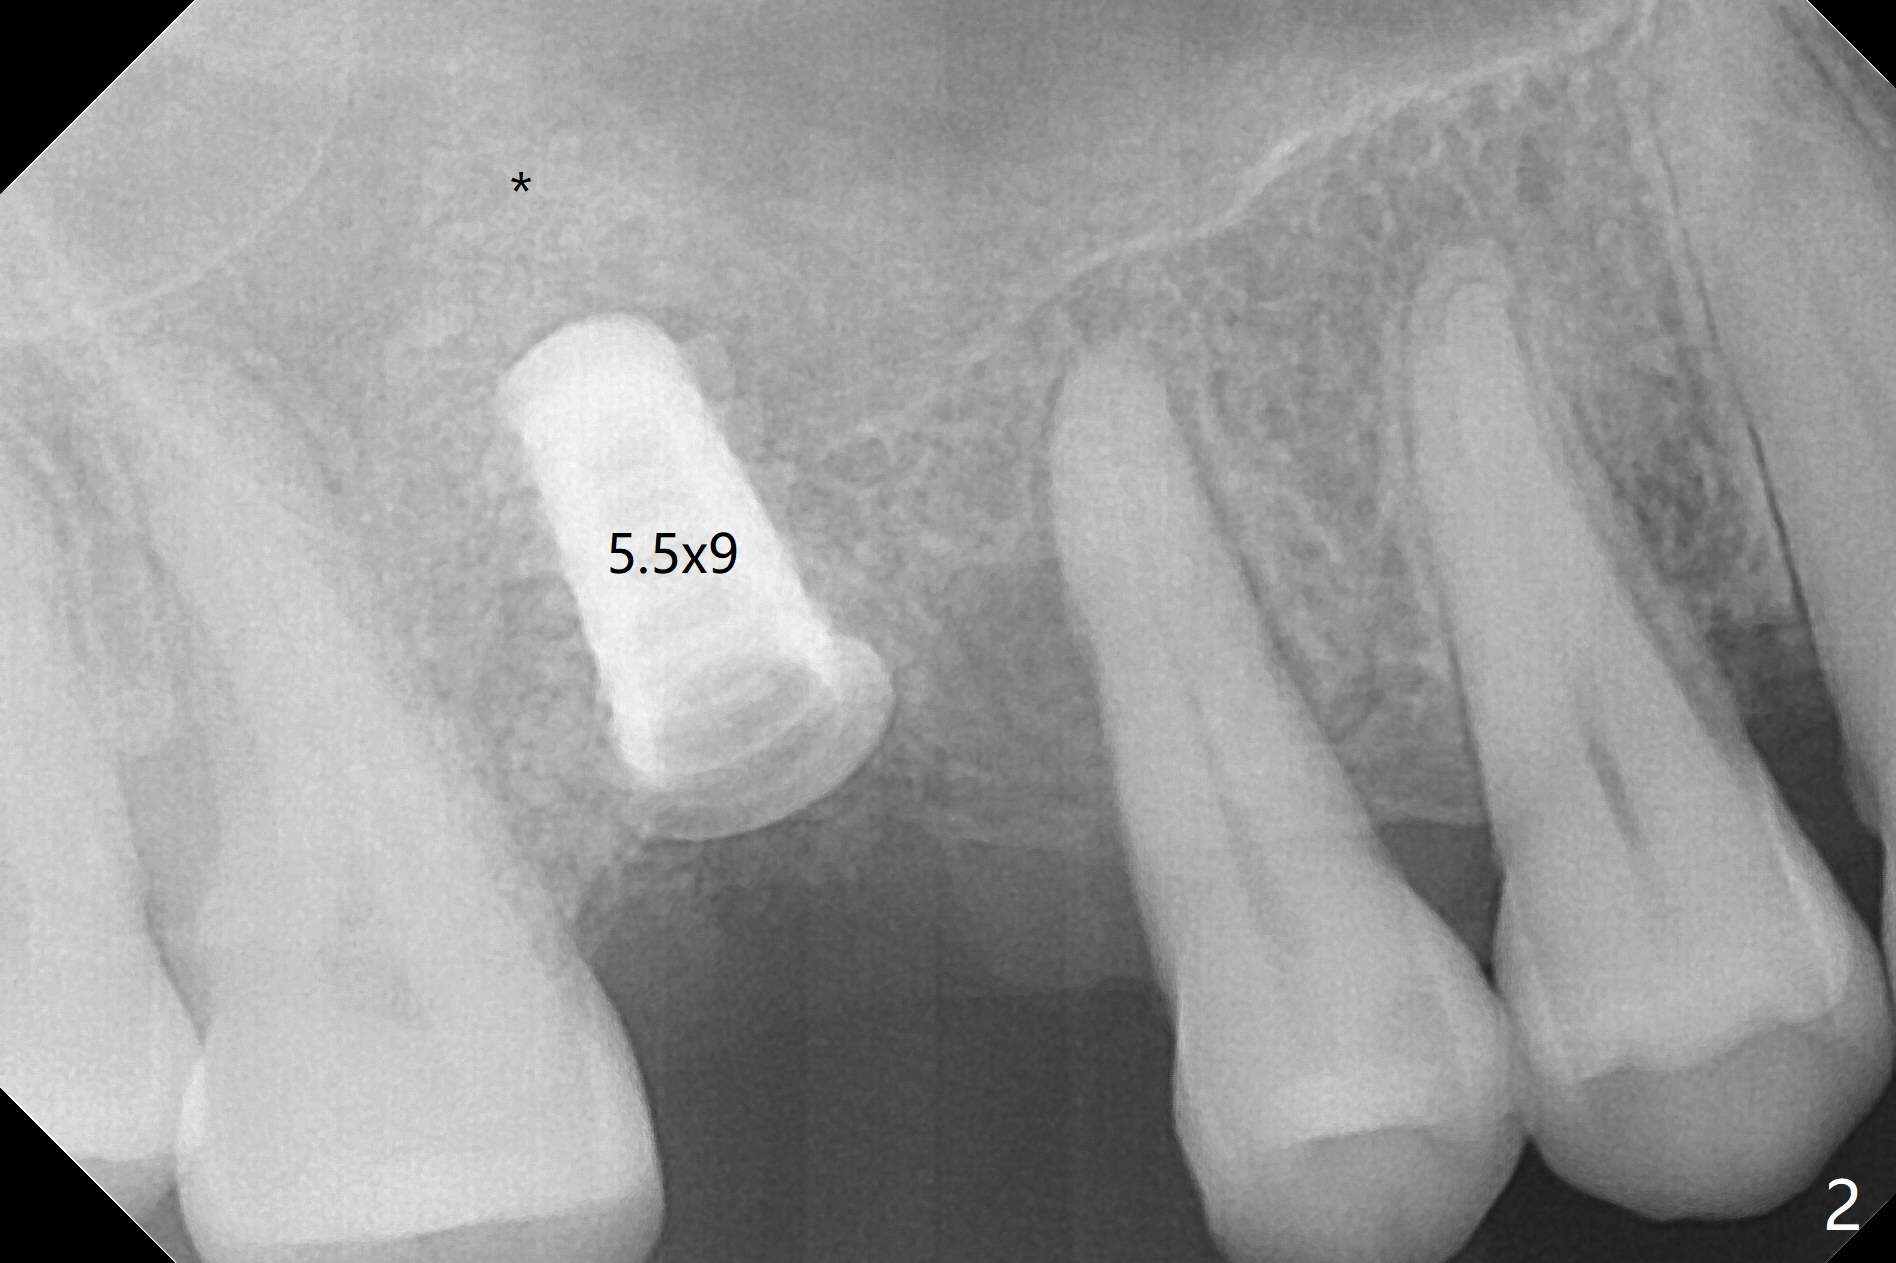

After extraction and debridement, osteotomy is initiated in the mesiobuccal socket free hand. Since the remaining bone is ~ 2 mm, the sinus floor is perforated suddenly. Fortunately the sinus membrane is not, as related to its thickening (similar to water ballooning, without symptom). Use 2-3.5 mm drills to enlarge the bony perforation (mainly lateral movement), followed by pushing bone graft upstairs with a curette (Fig.1 *); insert a 4x9 mm dummy implant (Fig.1) to determine the length of the final implant (Fig.2,3). A drawback of this case is the low torque (<20 Ncm), considering the thin bone. Following deeper implant placement, a 5.2x6(2) mm temporary abutment is placed for an immediate provisional to keep large amount of bone graft in place (Fig.3 *). There is no pain 1 week postop, while the immediate provisional remains stable partially because of the temporary abutment (Fig.4 ^). Four months postop, the temporary crown is loose. After removal of the temp and the temp abutment, gingival cuff is erythematous. A 6x4 mm healing abutment is placed. The bone graft (Fig.3 *) appears to have attached to the root of the neighboring tooth and the implant threads 7 months post op (COVID 19, Fig.5 arrowheads)). The bone graft appears to continue to merge with the neighboring root, bone and implant 10 months postop (2.5 months post cementation, Fig.6). The bone graft in the sinus seems to collapse and condense 10 months postop (Fig.7 *).